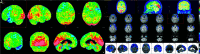

FIG 3.

Voxel-level imaging findings in lvPPA and dementia of the Alzheimer type (DAT) compared with controls. 3D renderings show regions of reduced FDG metabolism and GM volume in lvPPA compared with controls and in DAT compared with controls. Note, lvPPA demonstrates hypometabolism and focal atrophy primarily in the left lateral temporal and inferior parietal lobes (including the left angular and supramarginal gyri) and left precuneus and left posterior cingulate gyrus. Adapted with permission from Madhavan et al. R indicates right; L, left.

FIG 4.

[18F] FDG-PET cortical surface maps demonstrate an abnormal FDG distribution pattern with moderate-to-severe hypometabolism in the left, lateral temporoparietal lobes including in the left precuneus and posterior cingulate gyrus (A), with corresponding disproportionate cortical atrophy in the lateral left temporoparietal region visualized on brain CT (B), findings are further supported by a semiquantitative FDG-PET analysis using z scores calculated in comparison with age-matched cognitively healthy controls, demonstrating markedly decreased values in the left parietal and left lateral temporal regions, including in the precuneus and posterior cingulate gyrus (B).